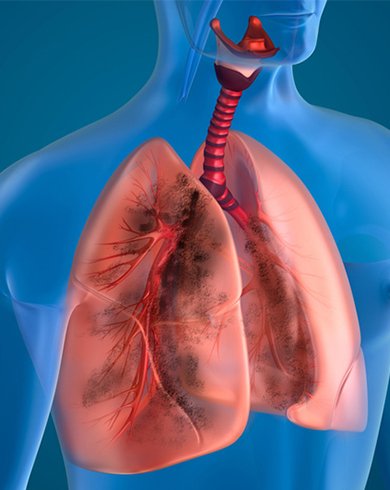

Areas of Expertise